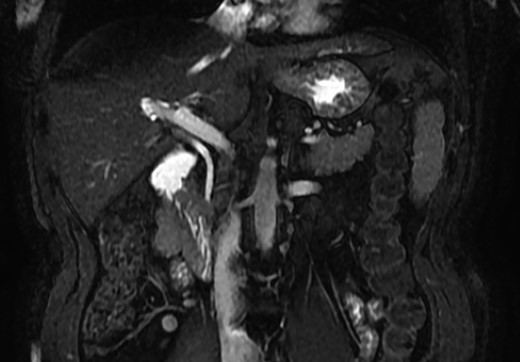

A magnetic resonance cholangiopancreatography (MRCP) confirmed the absence of gallbladder and of the cystic duct and artery (Figs 4–6). No other abdominal anomaly was identified.

MRCP coronal image showing the common bile duct, portal vein, duodenum, liver and other close structures; there is no sign of gallbladder.